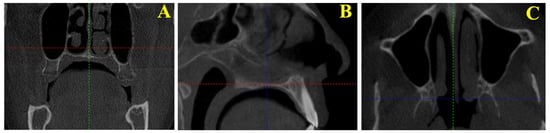

2.2. Standardization of Images

2.3. Measured Morphometric Parameters